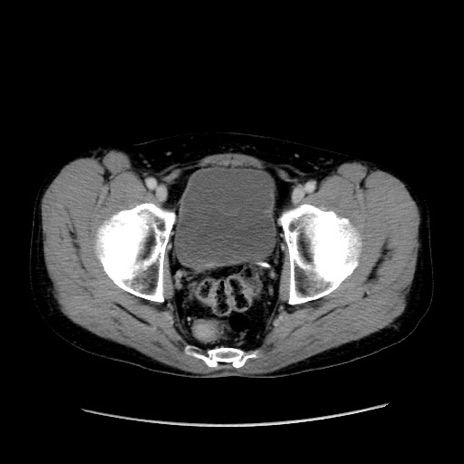

症例37(横断像)

【症例】40歳代 男性

【主訴】腹痛

【現病歴】4時間ほど前に電車に乗車中に臍部上より腹痛出現。徐々に増悪し起立困難となり、救急外来受診。生ものは数日食べていない。今朝お雑煮を食べた。

【身体所見】BT 36.8℃、BP 117/84mmHg、HR 91/min、SpO2 97%、苦悶様、腹部:臍上部広範囲圧痛あり、反跳痛±

【データ】WBC 8100、CRP 0.03